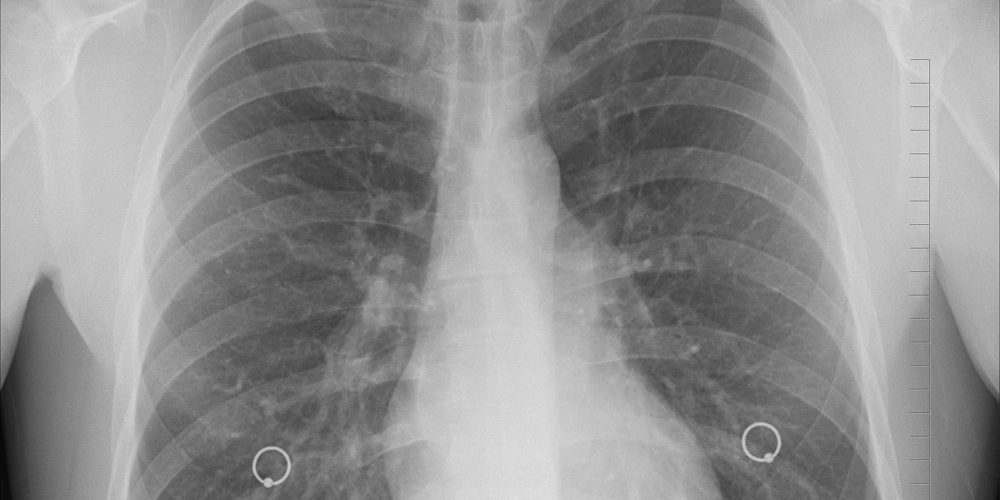

Врачи рассказали, как лицо выдает онкологию легких

По информации издания, к симптомам рака легких относят затрудненное дыхание, кашель, головные боли и неприятные ощущения в области грудной клетки. Также на прогрессирование злокачественной опухоли могут указывать и внешние признаки, а именно опухшее лицо.

Сообщается, что опухоль может давить на верхнюю полую вену — важнейший кровеносный сосуд в организме человека, по которому кровь доставляется от верхней части тела обратно к сердцу. Но, если кровеносный сосуд блокируется, возможно, из-за увеличившегося злокачественного новообразования в легких, то появляются характерные отеки лица, отмечается в статье.